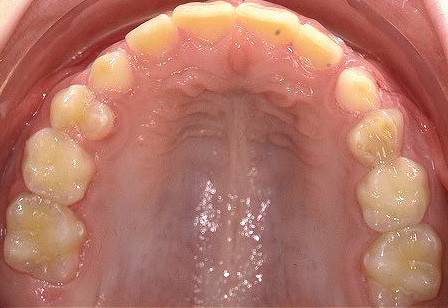

Klinisches Fallbeispiel 2 (Abb. 2a–y)

Distalbiss und tiefer Biss bei einem zwölfjährigen Mädchen. Die Behandlung erfolgte mit Invisalign und Precision Wings. Insgesamt waren zwei Schienensätze notwendig. Die Gesamtbehandlung dauerte 18 Monate.Bei der Planung des ClinCheck wurde der tiefe Biss vorwiegend über eine Intrusion der Unterkieferfront behoben, um die Lachlinie der Patientin nicht negativ zu beeinflussen. Die Oberkieferfront wurde nur retrudiert, jedoch vertikal nicht intrudiert. Während der Phase des Mandibular Advancement wurde die Wirkung der Precision Wings durch den Einsatz von Klasse II-Gummizügen unterstützt. Schlussendlich wurde auch der hängenden Okklusionsebene durch eine einseitige Intrusion der Molaren im ersten Quadranten Rechnung getragen.